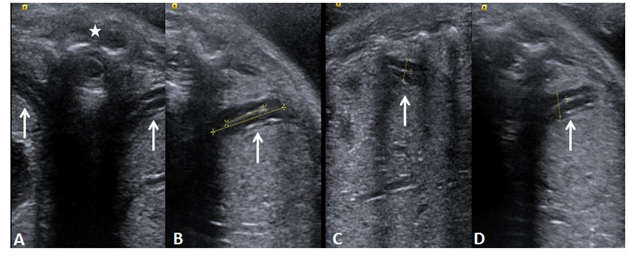

Figure 2 Elastographic images of the cervix at internal os (circles), (A) showing red -soft; (B) red and yellow-medium soft; (C) yellow and green-medium hard and (D) green and blue-hard. The color coding map is shown from the soft (SF) level to Hard level (HD) attached to the image A.

Cervical elastography

Elastography is an USG based imaging technique for assessment of the consistency of the cervical tissue/internal os. It is method of virtual palpation based on the concept of greater compression of the softer tissue on pressure as compared to the harder tissue. The gradient of the strain produced is displayed on color coded and a gray scale map. eSie Touch EI method is provided in Acuson S2000 USG (Siemens Healthcare, Erlangen, Germany) system which generates both gray scale and color coded maps across the soft to hard tissue consistency without application of pressure on the cervix. Most of the studies done previously have stressed on the assessment of the color coding of the region of the internal os.11‒13 Thomas et al.14 has mentioned the grading based on the color map,14 with red indicating soft, yellow (medium soft), green (medium hard) and blue or purple (hard). The grading was done on proportion of the colors on the color map. However, the cervical softening and prediction of the preterm is primarily based on red to yellow colors.11 Cervical elastography is done in the second trimester of gestation on patients presenting with clinical signs and symptoms of preterm labor and preterm premature rupture of membranes (PPROM) for the morphological assessment of the cervix. However, this Real Time Elastography (RTE) method is subjected to inter as well as intra observer variation; hence lacks standardization. Bishop’s scoring, cervical length and RTE of the cervix can be correlated for the assessment of the risk of preterm birth (Figure 3).